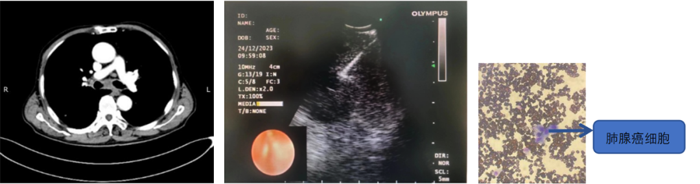

病例2

患者,男,70歲,近2個月來“活動后呼吸困難,近日又出現(xiàn)痰中帶鮮血”,收住院。胸部增強(qiáng)CT見“左肺下葉外周型占位,肺門、縱膈淋巴結(jié)腫大”。張強(qiáng)主任帶領(lǐng)團(tuán)隊(duì)討論分析患者病情,高度懷疑為腫瘤性病變,且普通電子支氣管鏡獲取組織困難,病變緊貼主動脈,經(jīng)皮肺穿刺活檢風(fēng)險大。為明確診斷及分期,決定為患者實(shí)施支氣管內(nèi)超聲引導(dǎo)下針吸活檢術(shù)(EBUS-TBNA)+電子支氣管鏡下病灶活檢+現(xiàn)場快速評價(ROSE)。術(shù)中ROSE快速診斷查找到肺腺癌細(xì)胞,手術(shù)過程順利。最后病理檢查明確診斷為肺腺癌,為患者的下一步治療確定了方向。

支氣管內(nèi)超聲引導(dǎo)下針吸活檢術(shù),是一種在電子支氣管鏡前端安裝超聲探頭的設(shè)備,結(jié)合專用的吸引活檢針,可在實(shí)時超聲引導(dǎo)下對臨近氣管或支氣管的胸內(nèi)病變進(jìn)行活檢。該技術(shù)不僅能實(shí)時觀察到病灶,同時可幫助確認(rèn)血管的位置,在提高穿刺診斷陽性率的同時防止誤穿血管,減少風(fēng)險,術(shù)中ROSE進(jìn)一步提高了取材效率,可實(shí)現(xiàn)精準(zhǔn)、高效、安全的明確診斷,又可大大減少對患者的損傷。(于 雪)